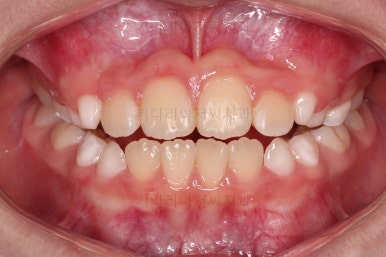

치료 종료!

총 13개월 걸려서 부산초등학생교정 위턱의 3차원적 성장과 앞니 가지런함을 다 이뤘어요.

앞니의 반대교합 뿐만 아니라 어금니 반대교합도 개선되었네요.

부산초등학생교정 전후 비교를 해보겠습니다.

부산초등학생교정 전후 모습을 보면 말 그대로 드라마틱한 변화네요.

특히 웃을 때 아랫니가 툭 튀어나와서 아랫니 위주로 보이던 미소가 완벽히 개선되어서 웃는 모습이 참 예뻐졌어요.

보호자분이 원하던 주걱턱도 개선되었고 초등학생 어린이 본인이 원하던 앞니 가지런함도 매우 좋아졌어요.